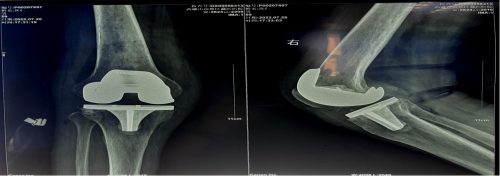

术后右下肢畸形明显矫正,假体位置安装精准

入院后检查后发现,患者营养不良并伴有低蛋白血症,右膝畸形严重,右侧膝关节内翻(内翻15度),是我们常说的“O形腿”,右侧膝关节周围压痛明显,膝关节活动范围10-90°。术前X光片提示右侧膝关节内翻畸形,股骨远端重度缺损。经多学科讨论及评估,医疗团队为患者行右侧人工全膝关节置换手术,从而缓解膝关节疼痛,改善膝关节功能,提高生活质量。

结合患者的情况,为保证患者获得最佳的治疗效果,术前完善CT三维重建,明确骨缺损部位,提前制定多套术中应对骨缺损处理的方案,并在术前准备了最小型号的假体,股骨侧垫块、延长杆及增强型内衬垫片。

术中,根据截骨后骨缺损情况,选择使用了残留骨块按缺损大小填充植骨,予以使用2.4mm松弛骨螺钉加强固定,就不需使用昂贵的延长管及垫块等材料这样的手术技巧减轻患者经济压力同时又巧妙的保证了手术效果。术后患者根据个性化的康复锻炼方案,恢复良好。